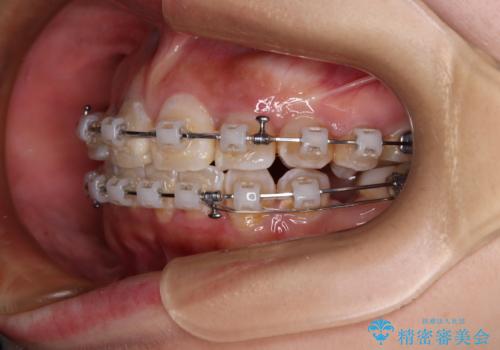

- 矯正装置

- 審美装置

- 2年3ヶ月

下顎は第二小臼歯を抜歯したため、治療期間が長期化すると思われましたが、大臼歯が後方に傾斜していたため、容易にスペースを閉じることができ、2年強で治療を終えることができました。